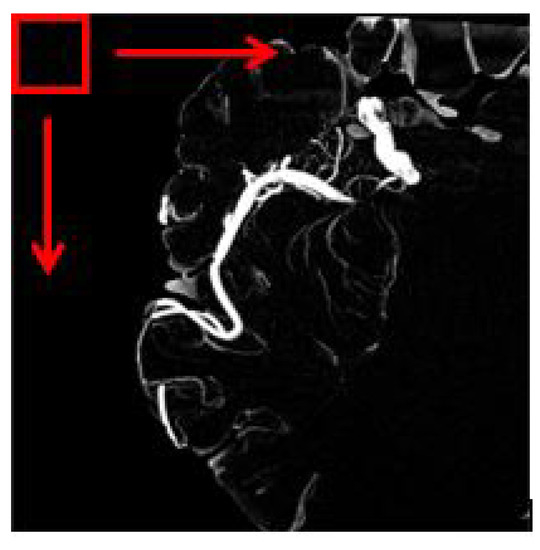

3.6. Vessel Enhancement

4.4. Feature Extraction